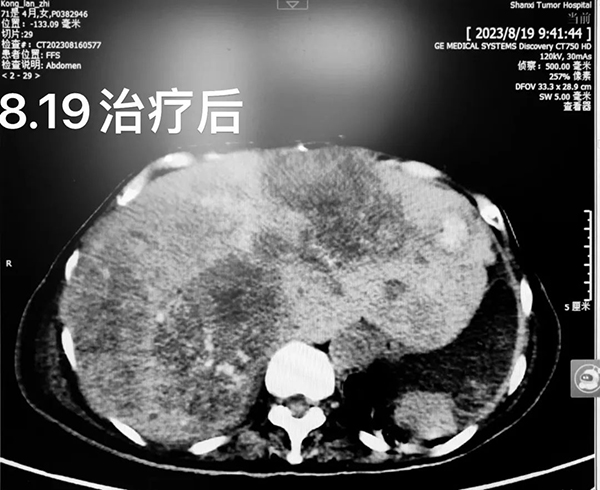

患者女性,71岁。2019年6月,因便秘于外院完善相关检查,7月行全身麻醉下腹腔镜下直肠癌切除术+肝左外叶部分切除术,术后病理示:直肠腺癌。术后给予XELOX方案全身化疗9周期。2021年3月,因肝转移合并右肺转移,给予伊立替康为主的全身化疗3周期,后行肝转移灶切除术。术后病情控制可。此后一直中药汤剂治疗。2023年9月,出现全身浮肿伴黄疸、谵妄及意识障碍,就诊于中医院,治疗期间下病危通知。在生死关头,患者家属抱着最后一搏的心态转入我院特需医疗部治疗。

患者转入我院特需医疗部时全身浮肿伴黄疸、谵妄及意识障碍,一般情况差,重度营养不良伴消瘦。薛艳峰主任带领医护团队第一时间查看患者病情,经过紧急充分的评估,初步诊断:直肠恶性肿瘤、肝、肺、骨继发恶性肿瘤、重度营养不良伴消瘦、肝功能不全、重度低钾血症、低钠低氯血症、低蛋白血症肾上腺皮质功能减退症。医护团队积极商讨并制定出最适合的治疗及护理方案:心电监护、间断皮肤及造瘘口护理、翻身拍背、监测血糖、血气,予保肝、补充白蛋白、肠内营养支持、纠正电解质紊乱、补液、利尿、抗凝、护胃等治疗。